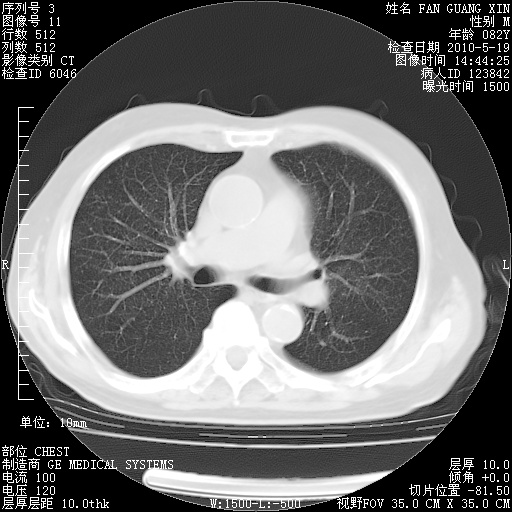

复查肺部CT,明显好转。为什么发热呢?

治疗3周后的肺部CT